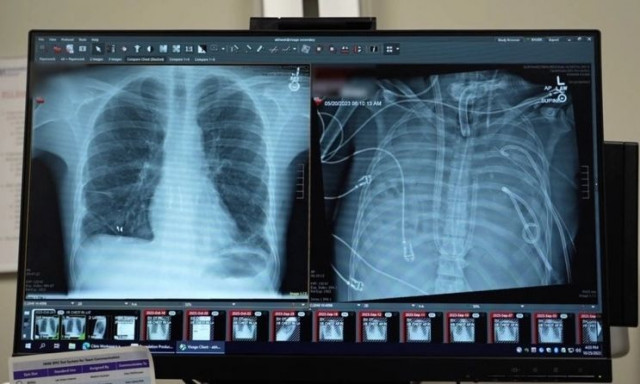

Γιατροί στις ΗΠΑ χρησιμοποίησαν πρωτοποριακό σύστημα «τεχνητών πνευμόνων» για να κρατήσουν ασθενή στη ζωή επί δύο ημέρες, έως ότου βρεθεί μόσχευμα.

Για δύο κρίσιμες ημέρες, γιατροί κατάφεραν να κρατήσουν έναν βαριά ασθενή στη ζωή χρησιμοποιώντας ένα πρωτοποριακό σύστημα «τεχνητών πνευμόνων», ανοίγοντας νέες προοπτικές για ασθενείς που περιμένουν μεταμόσχευση και δεν μπορούν να επιβιώσουν με τα υπάρχοντα μέσα υποστήριξης.